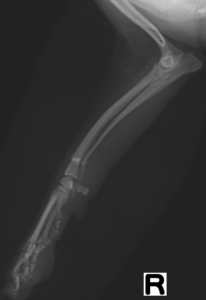

症例1:パピヨン、7ヶ月齢、目を離していたらキャンと鳴き右前肢挙上。

術前X線画像:右橈尺骨骨幹部骨折

手術所見:Fixin micro ストレートプレートによる整復・固定